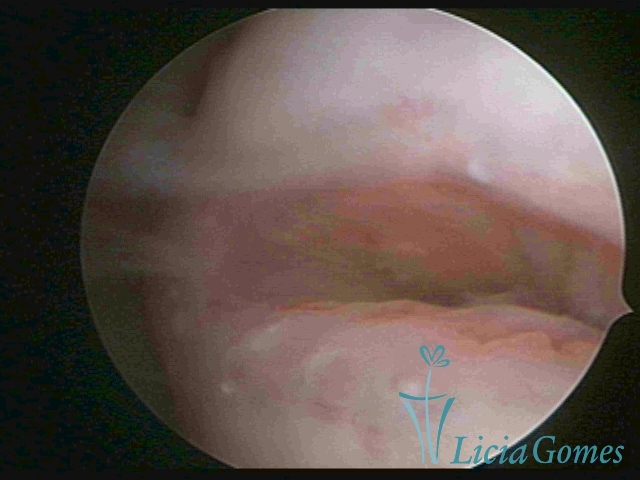

Segunda porção ou setor médio

No terço ou setor médio do canal cervical perdemos o detalhe das papilas, sendo possível a visualização de pregas e criptas. Normalmente observamos os sulcos longitudinais, que são os tecidos mais compactos, com a superfície mais vascularizada, cujos vasos seguem o seu trajeto.